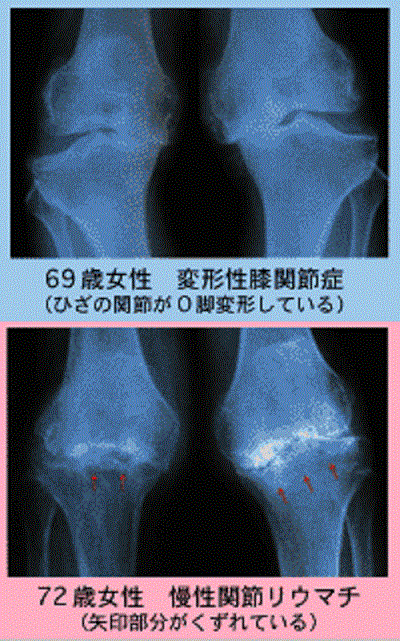

(※画像引用元 日本医師会HP)

ちなみに、中高年以上に最も多い腫れと痛みは「変形性関節症」(写真上)で、関節の軟骨がすり減ったものです。また、「慢性関節リウマチ」(写真下)は膠原病の一種で、朝のこわばり、左右対称の腫れと痛みなどが特徴です。